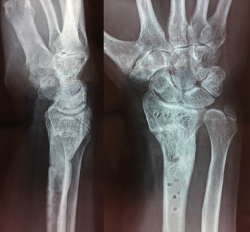

Figura 1. Radiografía simple y tomografía computarizada de fractura.

Se realiza radiografía simple y tomografía axial computarizada (TAC) (Figura 1). Se llevó a cabo la osteosíntesis con una placa volar Acu-Loc 2® distal ancha larga de Acumed y aporte de hueso de banco liofilizado en el foco metafisario. Se consiguió una reducción correcta (Figura 2). La herida evolucionó sin incidencias y se mantuvo al paciente 3 semanas inmovilizado con férula en U bloqueando la pronosupinación (sugar tongue). Posteriormente, inició una rehabilitación progresiva, con uso de ortesis rígida de descarga y controles clínicos y radiológicos cada 4-5 semanas.